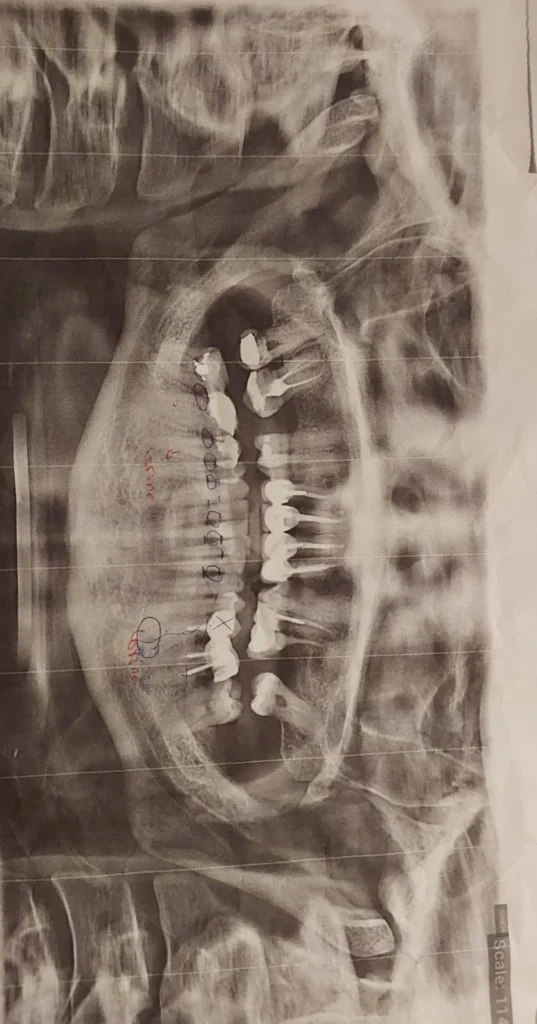

مجموعة من أضراس

Se connecterخاصك تعالجي التسوسات لي ممكن تكون مجرد حشو اسنان و ممكن تكون خاصها قتيل العرق حست التسوس فين واصل ، و من تقدري تشوفي التقويم